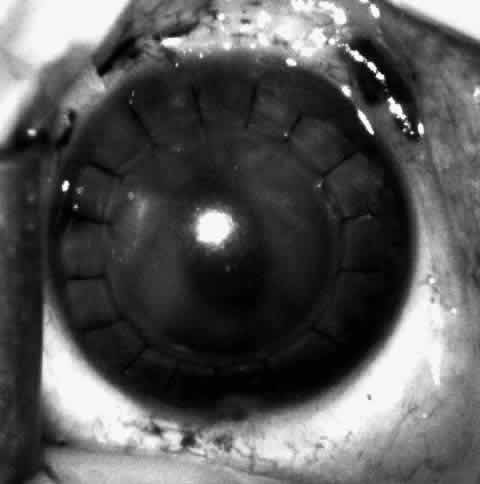

Children who have traumatic cataracts with corneal lacerations are well served by this procedure because the injury often destroys the capsular support that can be used to stabilize an intraocular lens.16–18 The epikeratophakia graft provides structural support for the weakened cornea and minimizes the induced irregular and regular astigmatism, in addition to correcting the optical error (Figs. 3 AND 4).

Fig. 3. Lacerated cornea with a hyphema. (Morgan KS, Ellis GS, Marvelli TL, Arffa RC: Epikeratophakia in children with traumatic cataracts. J Pediatr Ophthalmol Strabismus 23: 108–113, 1986)